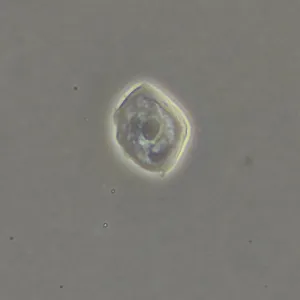

Фазово-контрастная микроскопия позволяет увидеть детали прозрачных образцов, которые практически не видны в светлом поле, и при этом не повреждать их окрашиванием. Метод применяют в разных сферах: медицине, биологии, ветеринарии, сельском хозяйстве, фармацевтике, экологии.